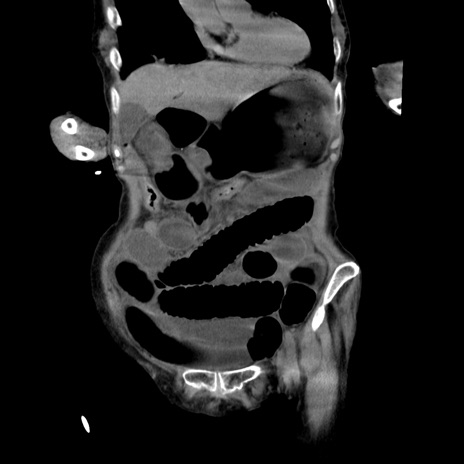

症例27(冠状断像)

【症例】80歳代女性

【主訴】嘔吐、腹痛

【現病歴】数時間前より嘔吐あり。心窩部痛出現し、徐々に右下腹痛あり。その後も数回嘔吐あり救急搬送となる。

【既往歴】左大腿骨頚部骨折手術

【身体所見】腹部は膨隆しているが軟らかく圧痛なし。腸雑音はやや亢進。

【データ】WBC 12000、CRP 19.05